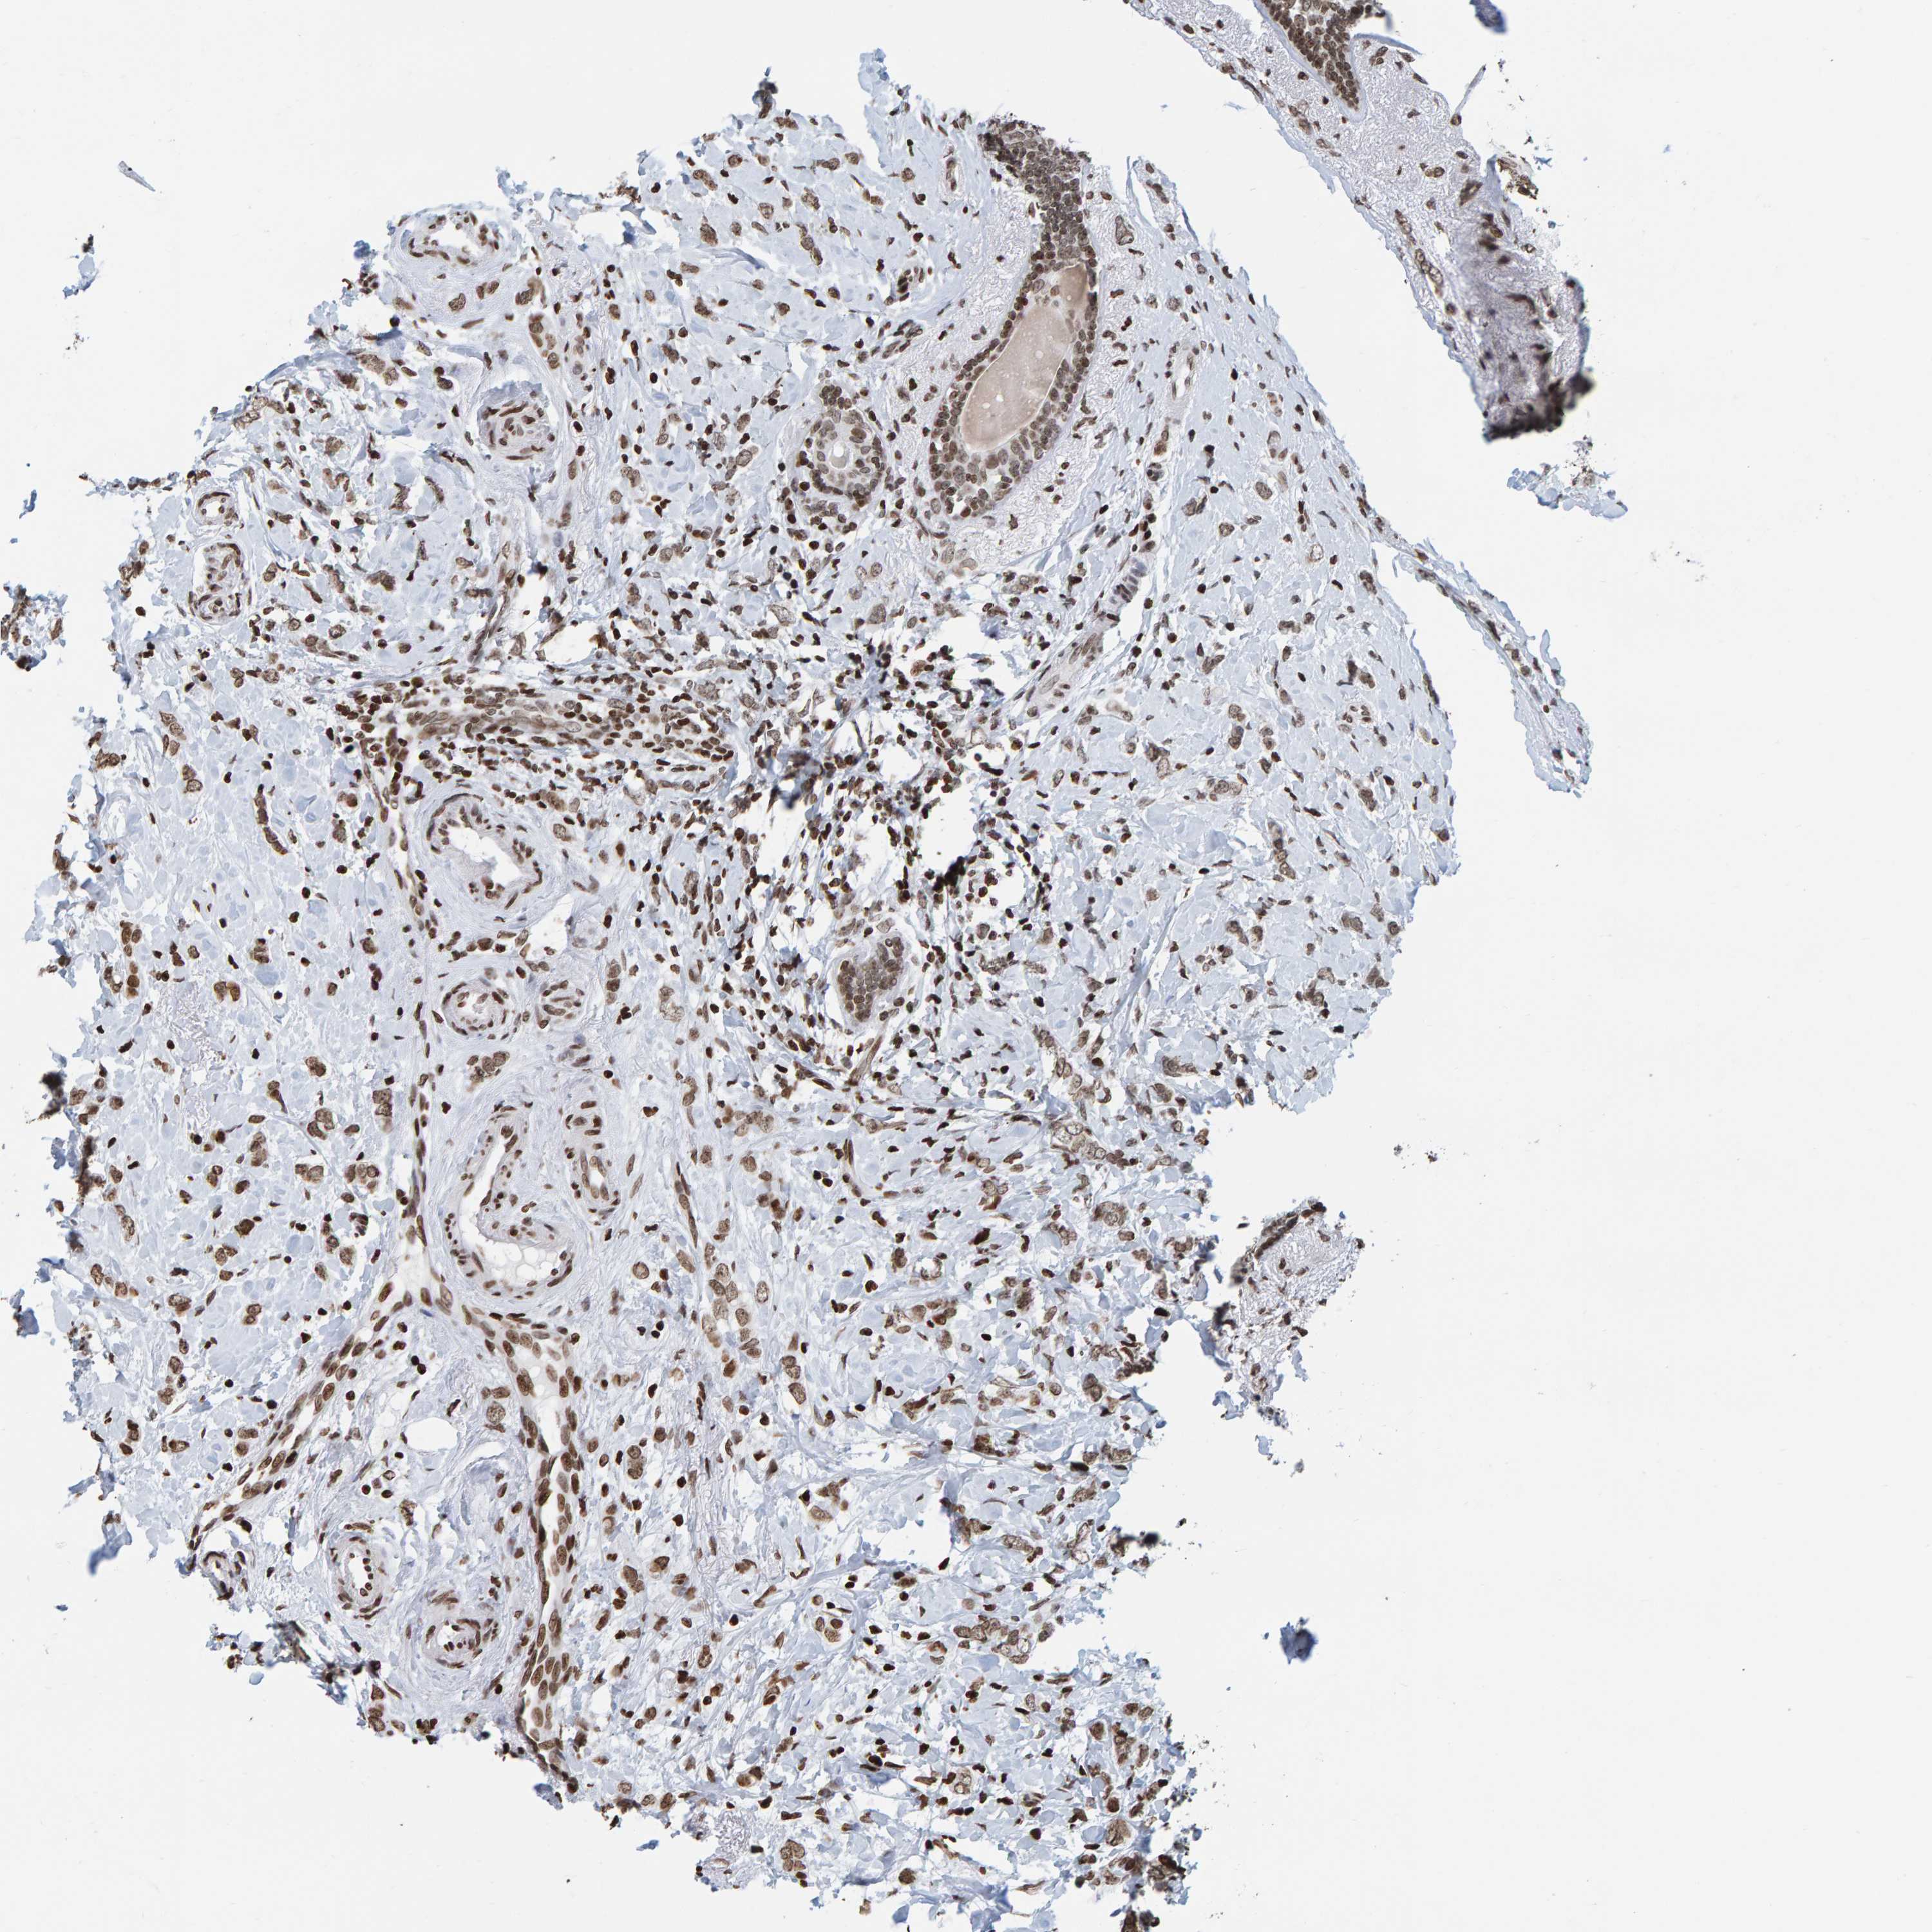

CANCER BREAST CANCER Show tissue menu

BRCA TCGA BRCA VALIDATION PROTEIN EXPRESSION